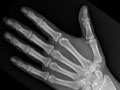

Extremity X-Ray

An extremity X-ray is a picture of your hand, wrist, arm, foot, ankle, knee, hip, or leg. It is done to see whether a bone has been fractured or a joint dislocated. It is also used to check for an injury or damage from conditions such as an infection, arthritis, bone growths (tumours), or other bone diseases, such as osteoporosis.